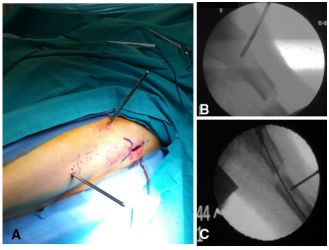

牵引后,将足部置于中立或轻微外旋位置,在正位和侧位通过透视评价骨折位置/复位。如果复位被认为是可以接受的,外科医生可以继续进行皮肤消毒和铺单;如果不能接受复位,通常远端骨折块处于向后移位状态;在这种情况下,为了便于复位和接骨,可以在远端骨折块下方放置拐杖,以抬起骨折块并获得远近端骨折对位(如图1A-C所示)。如果观察到水平的骨盆倾斜增加了近端骨折块的外旋,外科医生应该在术侧臀部下面放置沙袋或布单来纠正。

图1 A拐杖位于远端骨折块下方,便于年轻患者股骨粗隆下粉碎性骨折的复位;B股骨粗隆下骨折长髓内钉远端锁定的侧位片;C股骨粗隆下骨折长髓内钉远端锁定的正位片